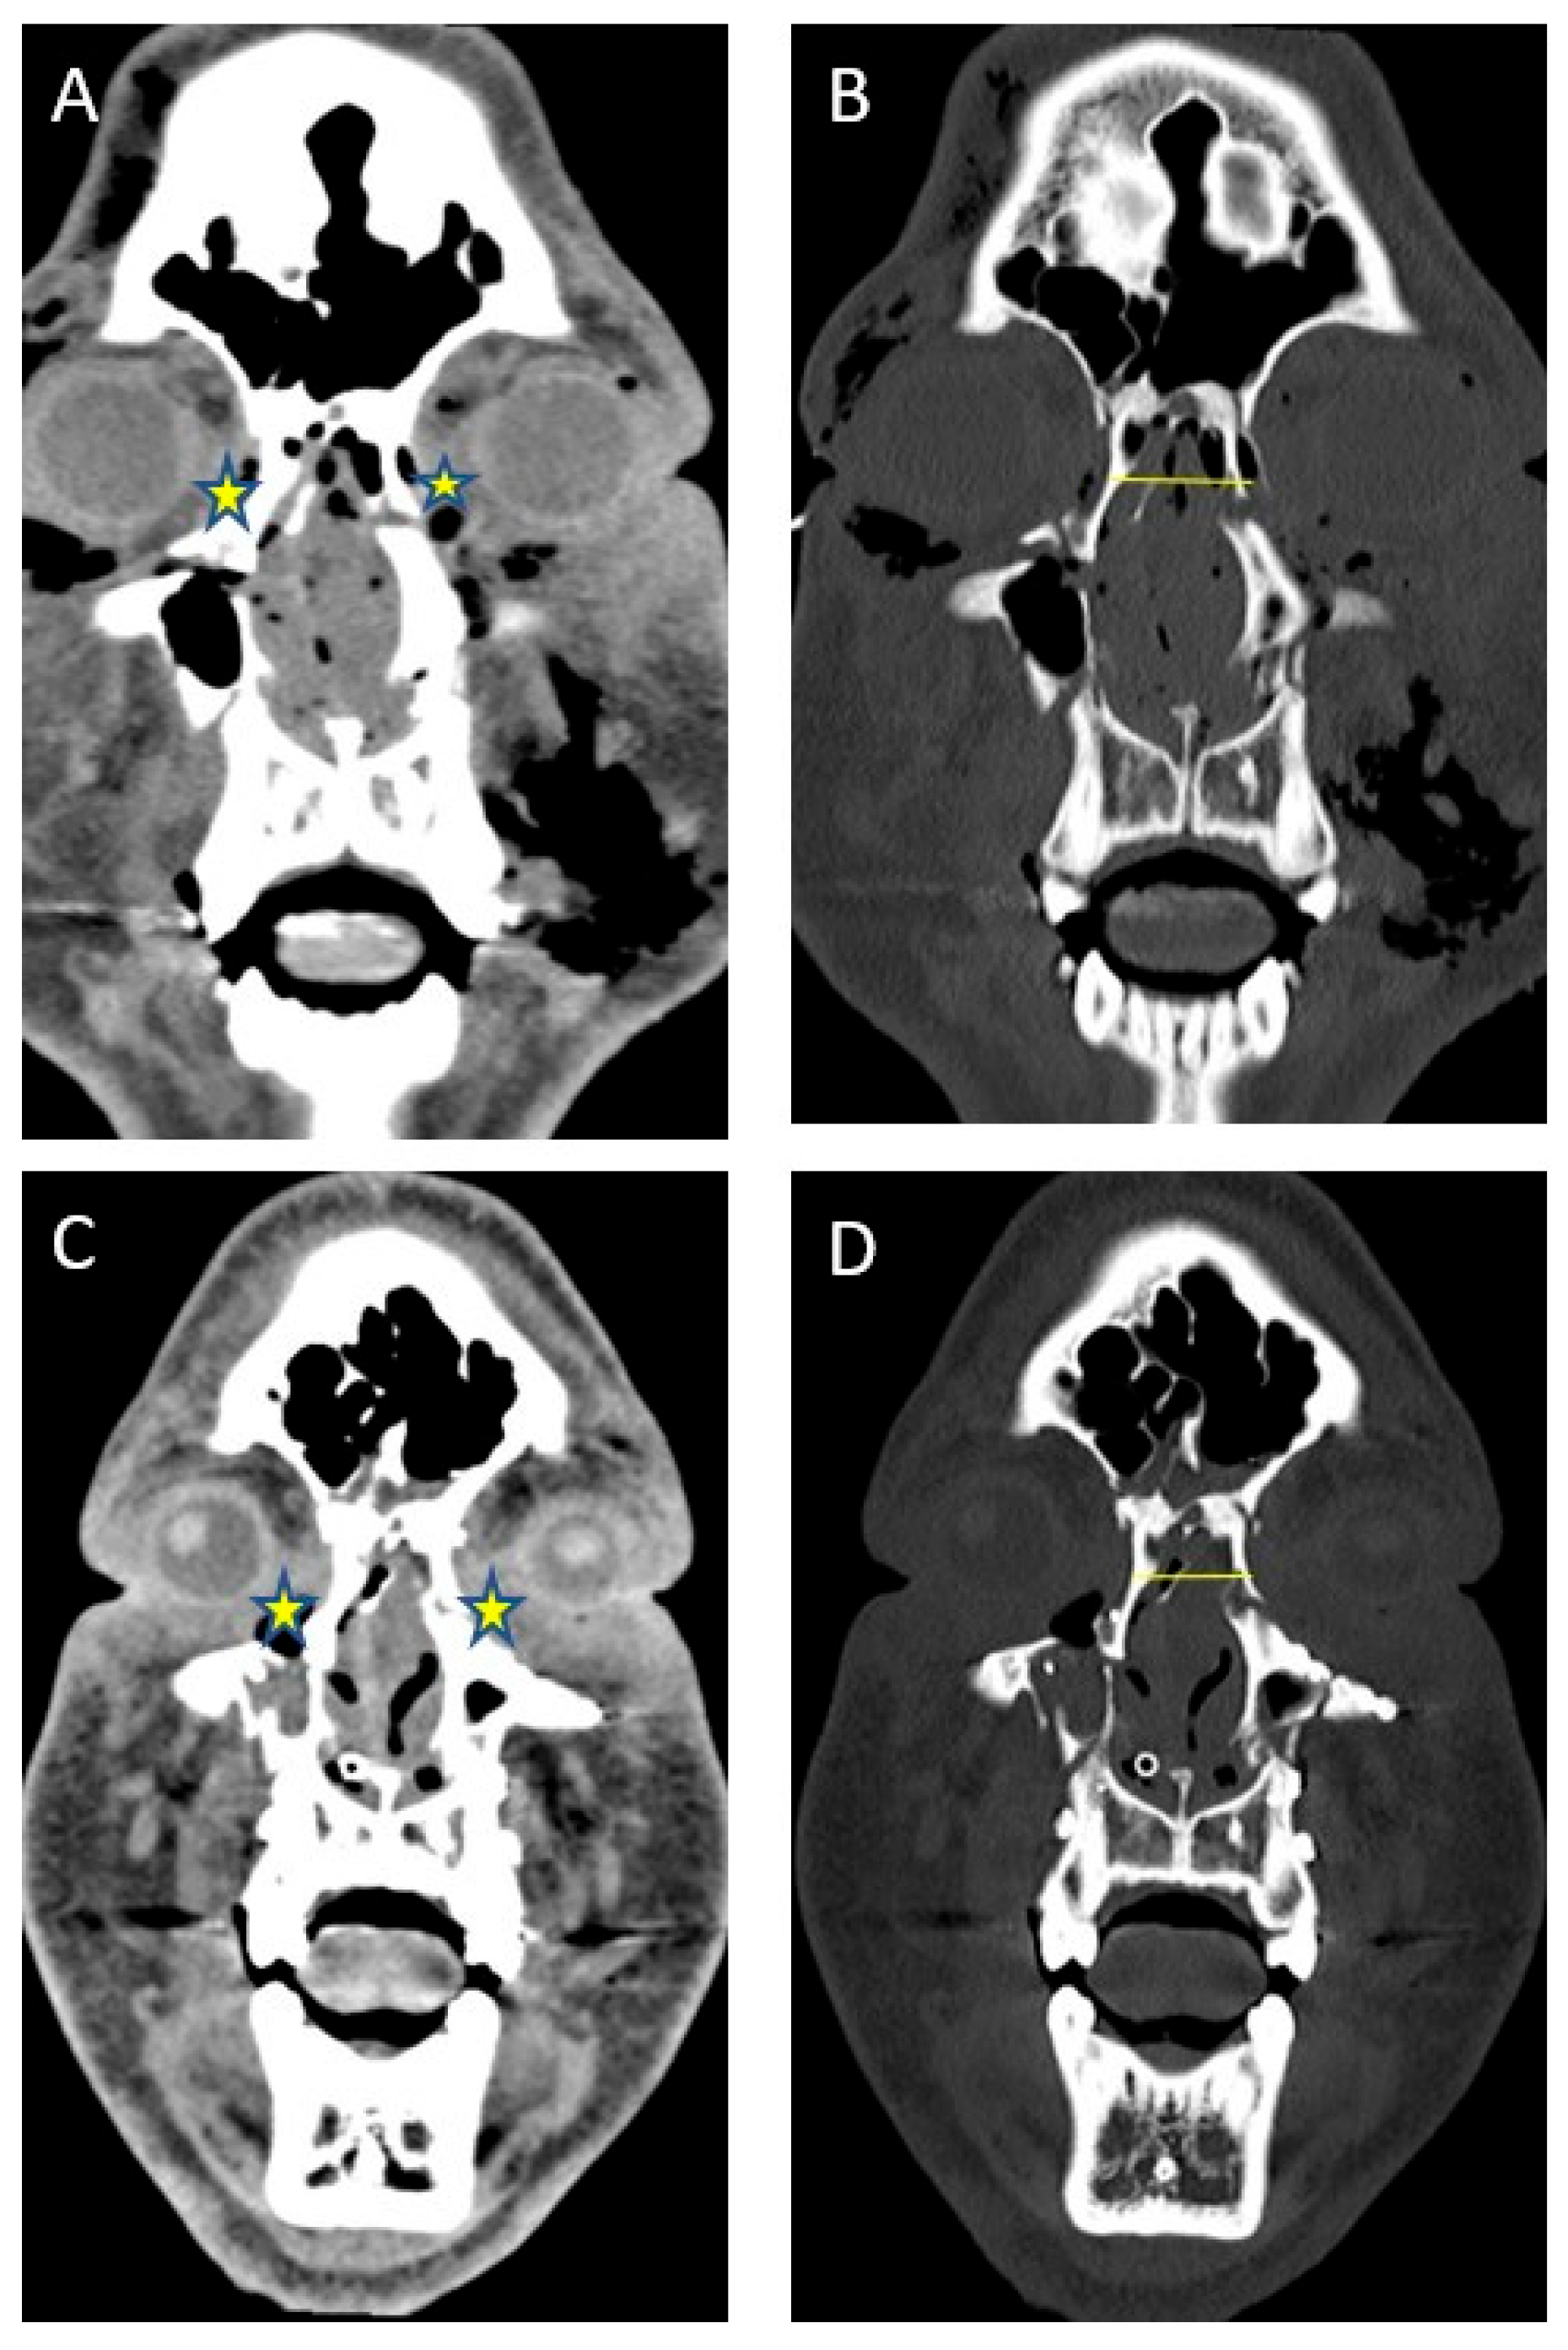

Figure 5. Type 3 NOE fracture CT imaging before and after intercanthal wiring.